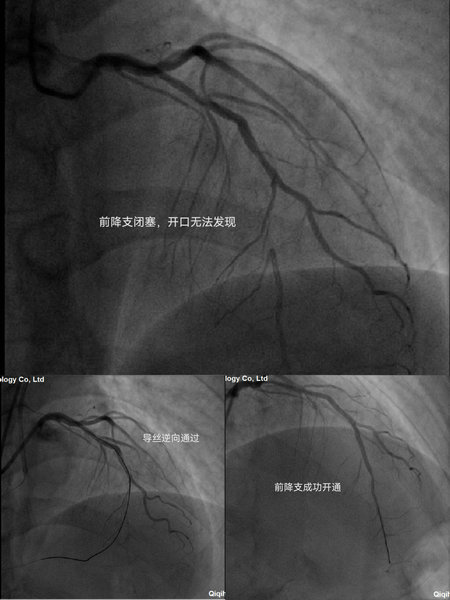

王先生入院后完善心电图,检查提示心肌缺血,完善24小时动态心电图可见ST段动态演变。吴晓杰主任、曹春明副主任考虑病人症状由冠脉血管病变导致,建议患者完善冠状动脉造影术检查。术中可见前降支中段以远闭塞,可见由右冠后降支给予逆向供血,病人前降支闭塞段无开口,完善IVUS检查仍无法找到开口,正向开通CTO难度大。吴晓杰主任、曹春明副主任考虑患者年龄较轻,开通前降支对患者远期预后受益颇大,若介入不成功则有可能转为冠状动脉搭桥术,故尝试进行CTO逆向PCI(冠状动脉支架植入术)治疗。经过不懈努力,成功使用导丝通过逆向供血处通过闭塞段,成功进行前降支冠状动脉支架治疗。患者术后无不适主诉。

影像图